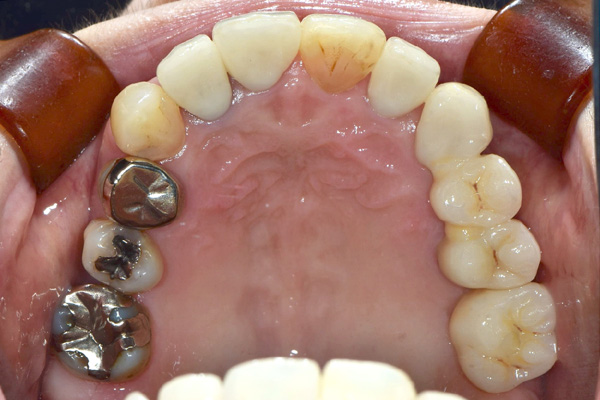

| 年代・性別 | 50代 男性 |

|---|---|

| 主訴 | 右下の歯がないのでインプラントをして欲しい |

| 治療期間 | 約6ヶ月 |

| 費用 | 600,000円 |

| 治療内容 | インプラント、骨造成、結合組織移植、セラミック修復 |

| 治療に伴うリスク | インプラント周囲炎 セラミックの破折、脱離 |